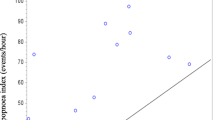

Tracheal ratios on expiration (expressed as percentage of minimum expiratory area to maximum inspiratory area) were 74.5 ± 8.6% in healthy individuals, and were significantly lower in stable COPD (57.5 ± 19.8%, 95% CI of difference 10.2 to 23.7%, p < 0.001). Tracheal area ratios were also lower in AECOPD (53.8 ± 19.3%, 95% CI of difference 15.2 to 26.0%, p < 0.001) (Fig. 1) than in healthy individuals. Tracheal area in AECOPD was similar to stable COPD and did not differ significantly (p = 0.355).